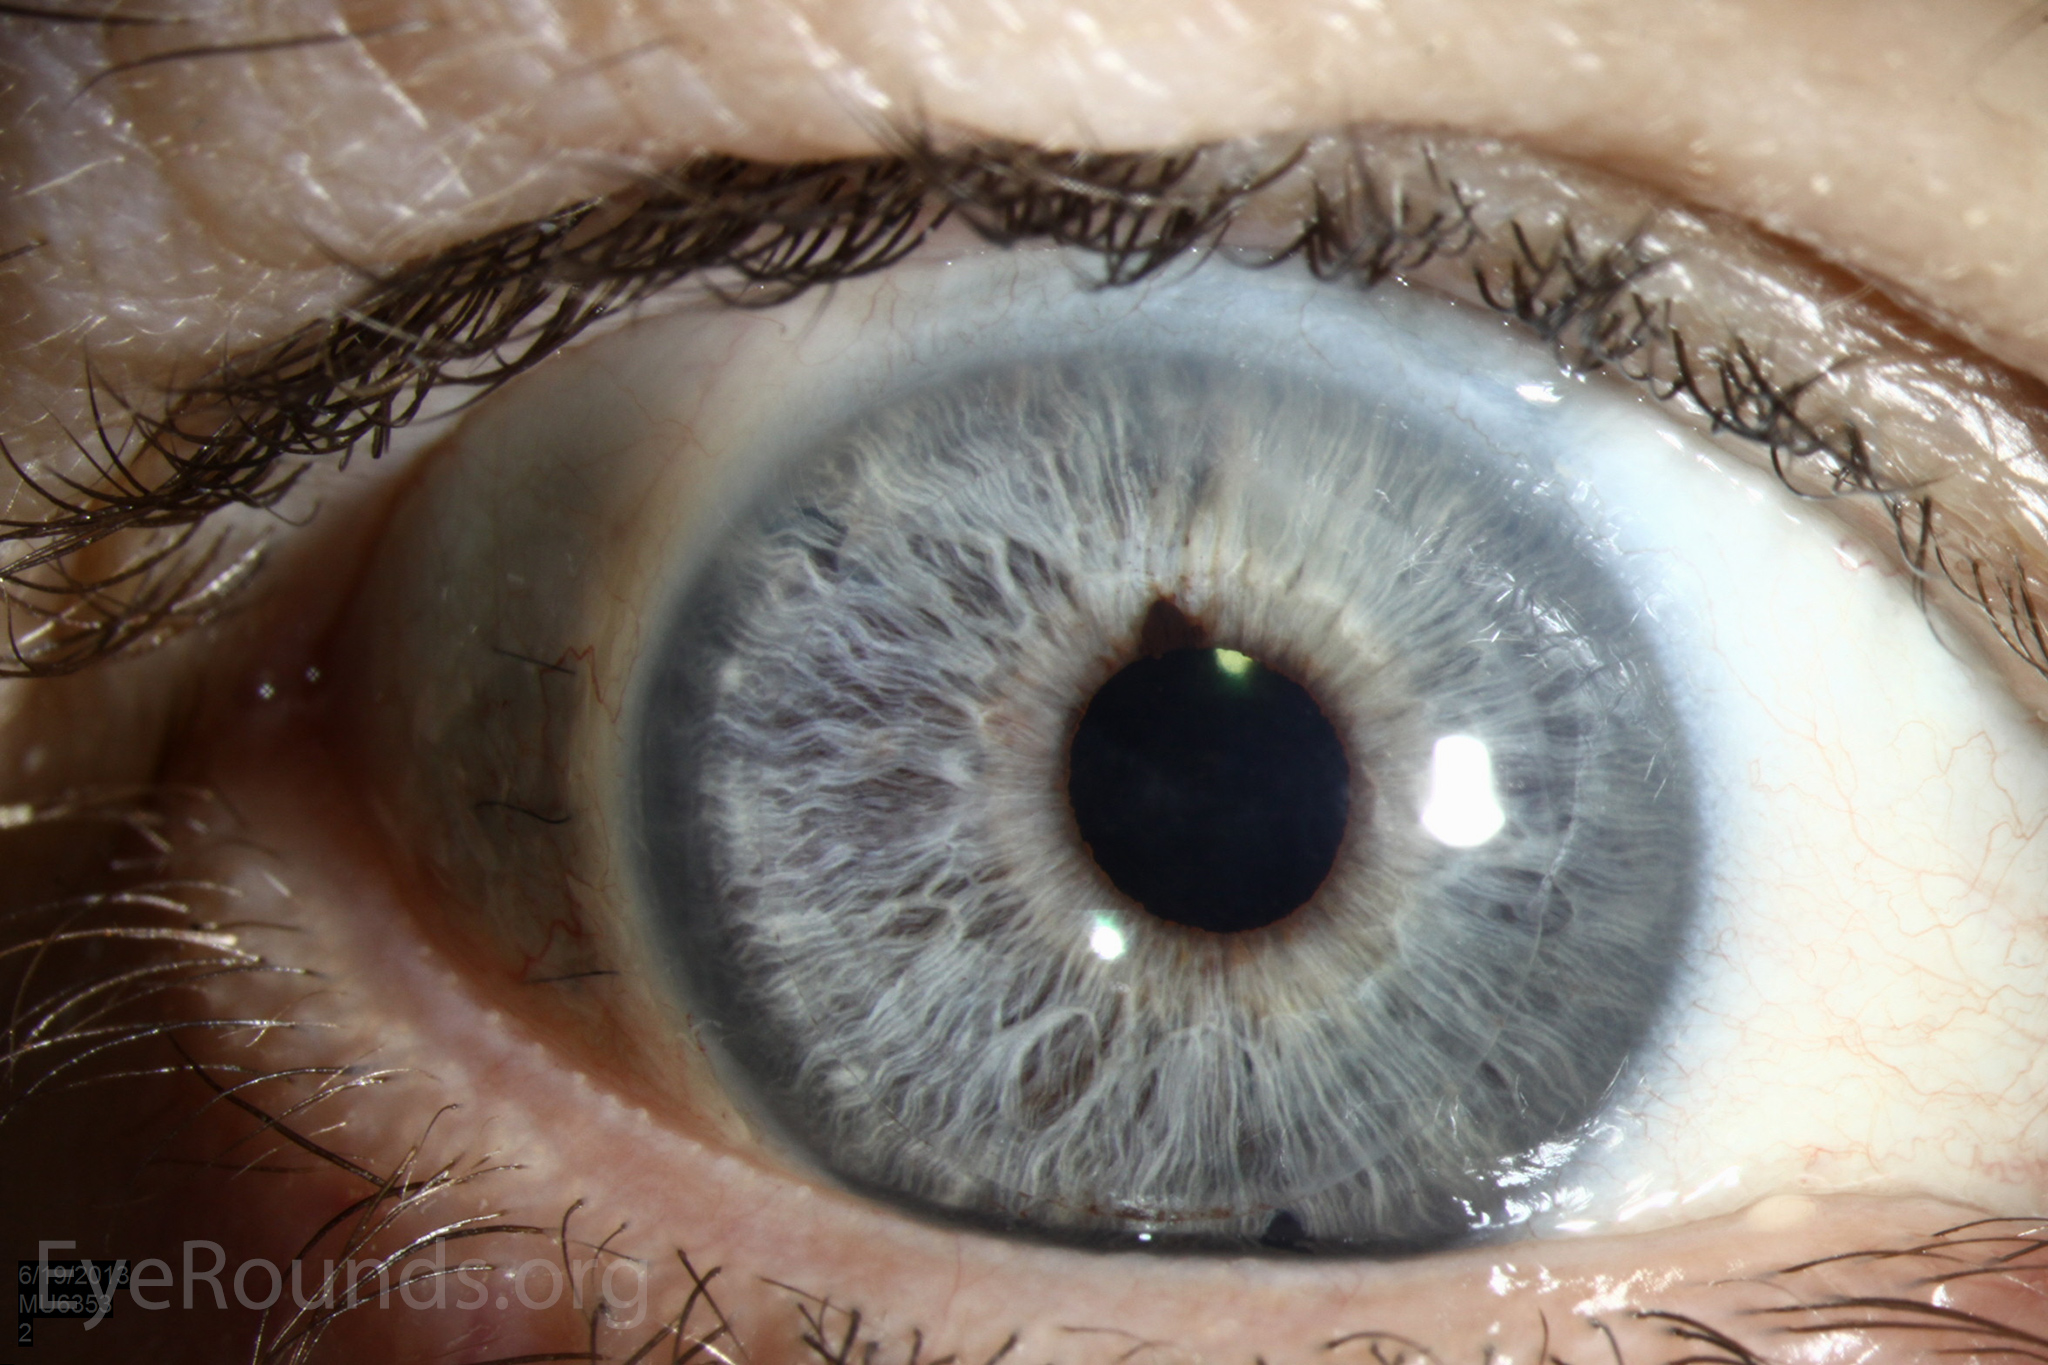

DALK is a partial-thickness cornea transplant procedure that involves selective transplantation of the corneal stroma, leaving the native Descemet membrane and endothelium in place. A trephine of an appropriate diameter is used to make a partial-thickness incision into the patient's cornea, followed by pneumodissection or manual dissection of the anterior stroma. This is followed by placement of a graft prepared from a full-thickness punch in which the donor endothelium-Descemet membrane complex has been removed. The intention is to preserve the patient's Descemet membrane and endothelium. Similar to PK, the graft is secured with interrupted and/or running sutures (Figure 5) and these are then selectively removed post-operatively (Figure 6).

DALK is useful for processes involving the corneal stroma in the presence of healthy endothelium. Examples include corneal ectasia (such as keratoconus in the absence of hydrops), corneal scars that are not full-thickness, and corneal stromal dystrophies (1, 15, 16).

Because it is not a full-thickness procedure, the resultant wound is stronger than that of a PK. Leaving the host endothelium intact significantly decreases the risk of endothelial rejection.

The surgery is more complex and difficult to perform than PK. If the Descemet membrane is perforated intraoperatively, the surgeon must convert to a PK. The "big bubble" technique makes dissection more consistent and is the preferred technique at our institution (12).